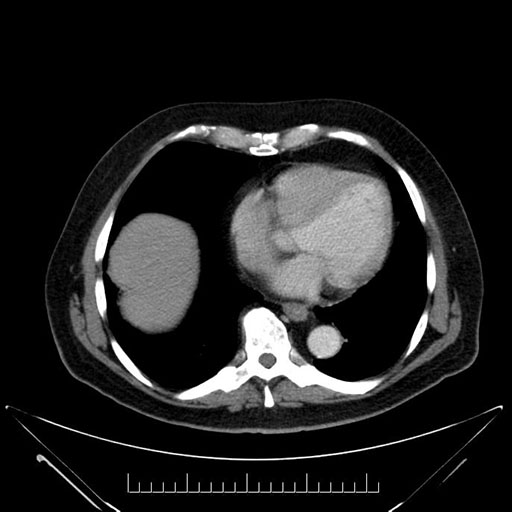

Imaging Analysis

Look through the patient's CT scan to identify any areas of concern for the necessary procedure.

Based on your CT findings, which issue(s) would give reason for "planned slowing down moment(s)" in this case?